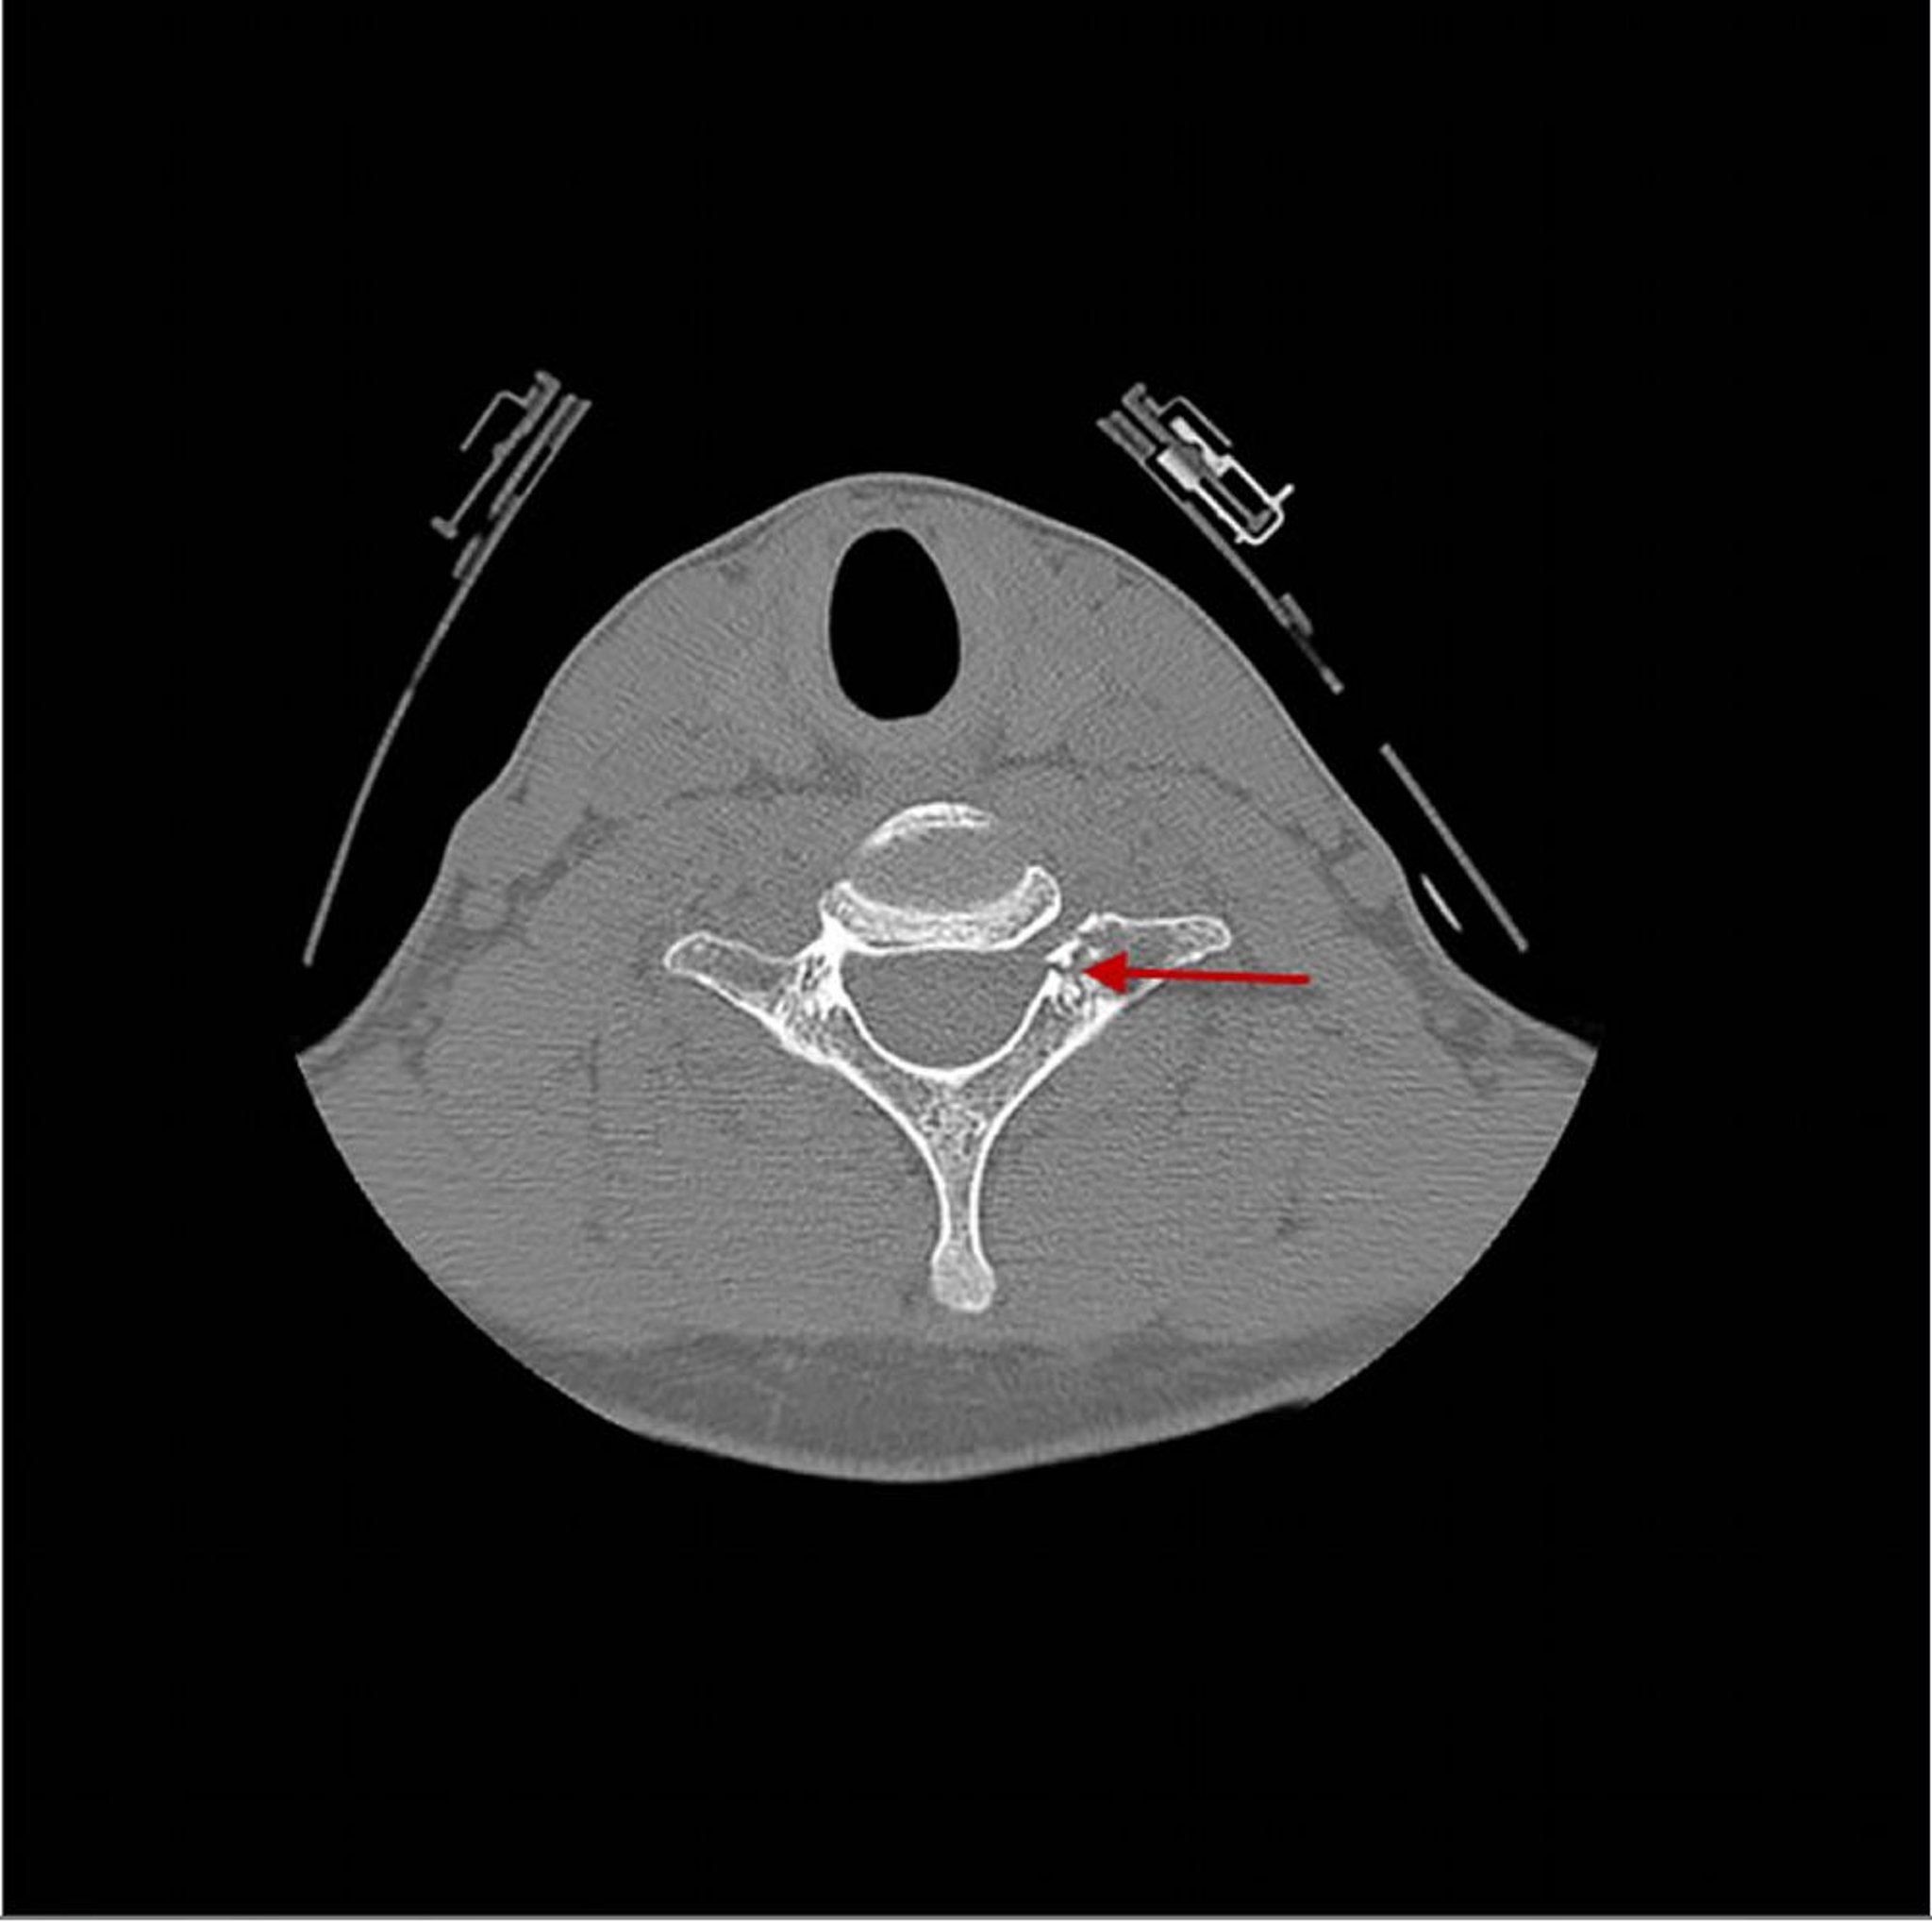

Frattura di una vertebra cervicale

Questa TC mostra una frattura (freccia) che attraversa la 7a vertebra cervicale appena posteriore al corpo vertebrale.